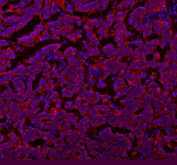

Immunofluorescent staining of SLC7A7 using anti-SLC7A7 antibody (red). SLC7A7 was detected in a paraffin-embedded section of human ovarian cancer tissue. Heat mediated antigen retrieval was performed in EDTA buffer (pH 8.0, epitope retrieval solution). The tissue section was blocked with 10% goat serum. The tissue section was then incubated with 5 ug/ml rabbit anti-SLC7A7 antibody overnight at 4oC. DyLight 594 Conjugated Goat Anti-Rabbit IgG was used as secondary antibody at 1:500 dilution and incubated for 30 minutes at 37oC. The section was counterstained with DAPI nuclear stain (blue). Visualize using a fluorescence microscope and filter sets appropriate for the label used.